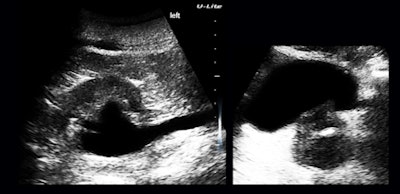

Figure 6: Apical four-chamber and mitral-valve views.I was thinking about the reflectors around the crux of the heart and how much of the apparent atrial volume disparity was a scan-plane effect when I continued looking and came upon something of more immediate concern (figure 7).

Figure 7: Hydronephrosis, hydroureter, and an abnormal prostate.I have the feeling that timely and expertly applied ultrasound, trusted fully by our referring colleagues, is a giant cost-saver by eliminating false alarms. We all focus on definite findings, whereas negative findings and normal appearances can be of enormous value in day-to-day practice.

I was entirely satisfied with equipment performance. I used the U-Lite exactly the way I would have used a max-performing high-end system, except both the patient and I were ambulatory and away from our usual haunts.